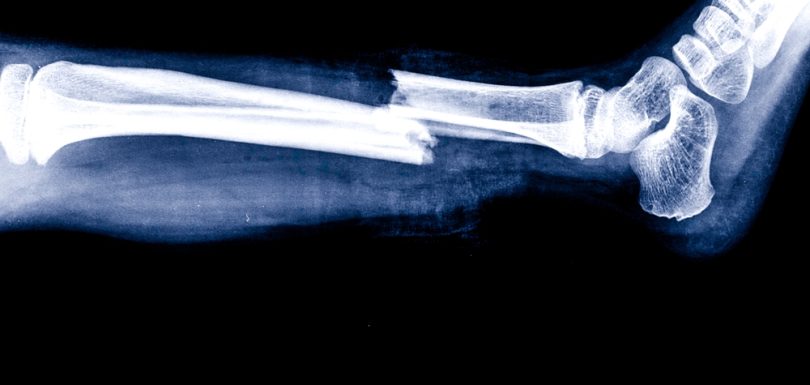

30 Apr By ADR Blog, X-Rays No Comments X-Ray Imaging Center Near Frederick, MD For Broken Bones And Sprains An X-ray imaging center near Frederick, MD can help evaluate broken bones, sprains, and other severe injuries. Continue Reading